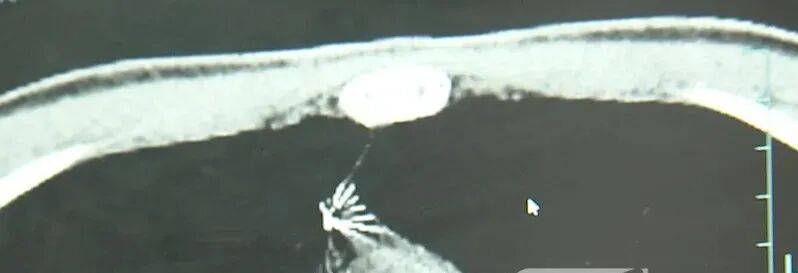

近日,安徽17岁小伙小陆参加征兵体检,胸片结果显示:胸腔内有一处金属高密度影,形态细长,像一根针。

进一步的CT检查确认,异物是一枚金属针,斜插在肺组织内,位置十分凶险。

杭州市第一人民医院心胸外科副主任冯兴说:“我们看到这个针的尖锐部,正好指向他体内的一个大血管,边上是上腔静脉和胸主动脉,因此这个针稍有不慎,就有可能造成周边血管的损伤,甚至危及生命。”